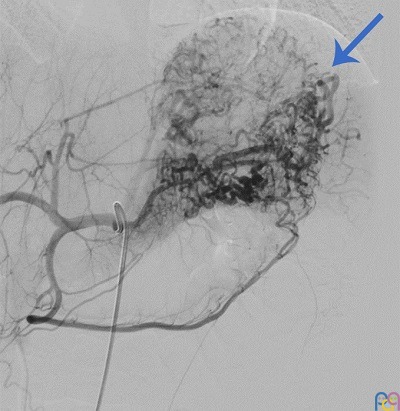

Ante dichos hallazgos se decidió traslado a nuestro centro, donde se realizó una arteriografía diagnóstico-terapéutica. La embolización de la malformación transcurrió sin incidencias (Fig. 1 y Fig. 2).